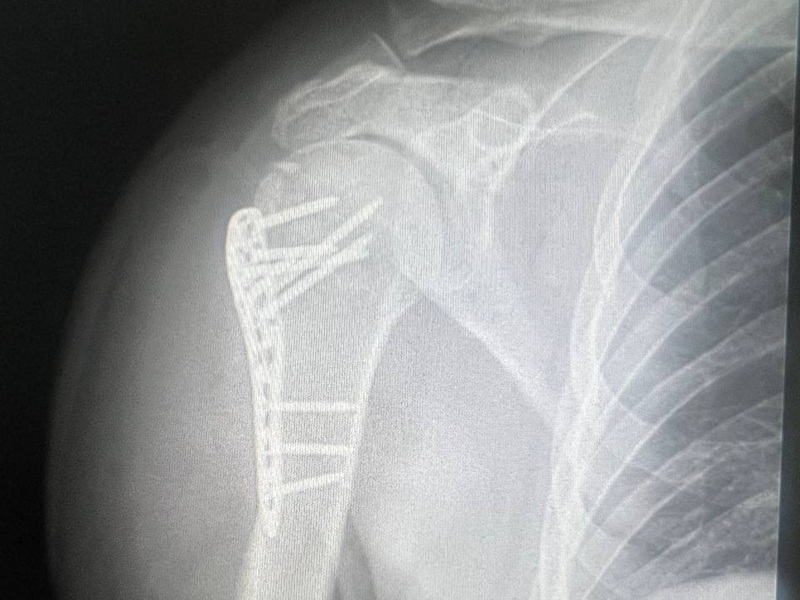

- наличие инородных тел или послеоперационных изменений (например, эндопротезов).

Хотя рентген не отображает мягкие ткани так подробно, как МРТ или КТ, он отлично справляется с первичной оценкой состояния костно-суставной системы. Для врача это инструмент раннего выявления патологий, сравнения снимков в динамике и контроля течения заболевания.

Чаще всего исследуют коленные, тазобедренные, плечевые, локтевые, голеностопные суставы и суставы кисти. Это связано с частотой травм и нагрузками на эти зоны. Также рентген делают для контроля состояния после протезирования или при артрозе.